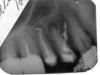

anynat Опубликовано 17 января, 2007 Поделиться Опубликовано 17 января, 2007 Уважаемые специалисты, очень требуется ваше авторитетное мнение.Доктор не смог пройти канал, когда-то запломбированный резорцином... Перфорация... Теперь настаивает на удалении зуба.Белое вещество в канале пятёрки и проникшее в ткани через перфорированную четвёрку- Витапекс. Собственно вопросы. 1. Стоит ли бороться за четвёрку -кроме перфорации у верхушки корня довольно значительная ...ммм... что? - киста? гранулёма? деструкция костной ткани? - для лечения которой собственно и пытались вскрыть канал. Если всё-таки есть шанс сохранить зуб, какой стратегии следует придерживаться?Имеет ли смысл оперативное вмешательство - резекция корня, кажется- если пройти канал не представляется возможным. 2 Насколько опасно для тканей, окружающих зубы то, что в них попал Витапекс? С благодарностью выслушаю ваши соображения по моей проблеме. Ссылка на комментарий

Bier Опубликовано 17 января, 2007 Поделиться Опубликовано 17 января, 2007 ну с гайморотомией вы загнули, воспаления в пазухе не видно, а материал рассосется. 4ку однозначно удалять, 5ку можно подумать об РВК. (резекция верхушки корня) Ссылка на комментарий